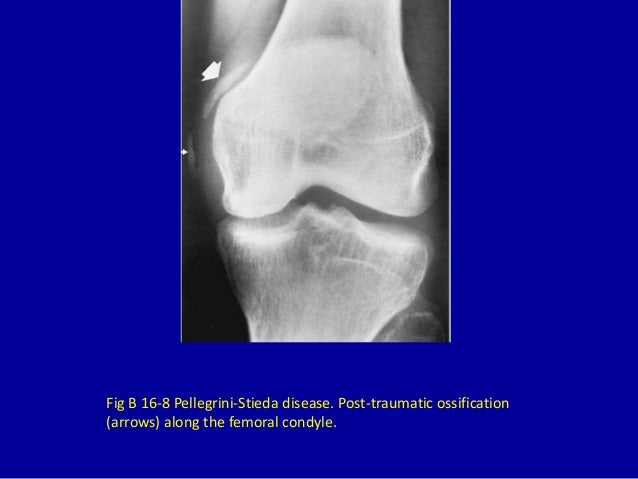

Pellegrini Stieda Disease / Pellegrini-Stieda lesion | Radiology Reference Article ... - Related online courses on physioplus.. One presumed mechanism of injury is. Contribution to journal › comment/debate. A heterogeneous disorder not synonymous with ossification/calcification of tibial collateral ligament. The diagnosis pellegrini stieda disease was made. It is a common incidental finding on knee radiographs.

It is a common incidental finding on knee radiographs. Pellegrini stieda syndrome is a medical problem which is characterized by pain, swelling and this herb is effective in the treatment of autoimmune disease where the immune cells of the body destroy. The diagnosis pellegrini stieda disease was made. Related online courses on physioplus. Contribution to journal › comment/debate.

A heterogeneous disorder not synonymous with ossification/calcification of tibial collateral ligament.